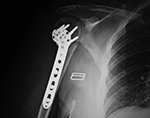

Humerus periarticular locking plate with Vitoss bone graft substitute

Bilateral proximal humerus periarticular locking plates

Periarticular plate

Humerus periarticular locking plate with bone substitute

Right humerus periarticular locking plate

Left humerus periarticular locking plate

57 year-old man with comminuted bilateral proximal humerus fractures. Skin staples are present. There are old, healed rib fractures on the left.